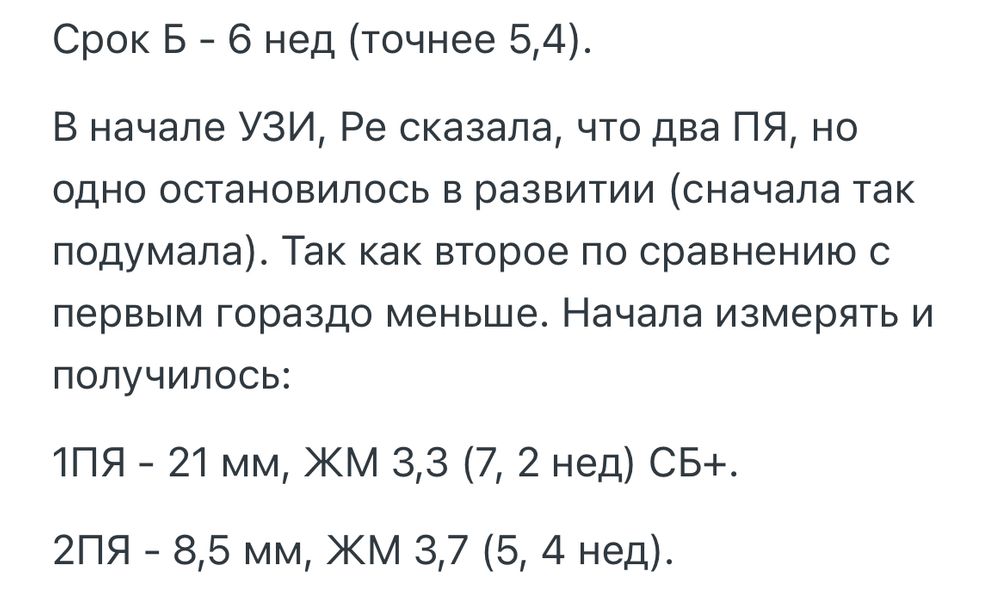

Мамочки двоен , у вас было отставание по первому узи ваших ПЯ и ЖМ? Я что-то сначала обрадовалась двум пузырикам , а потом зачем-то начала гуглить все остальное 🙈

Смущается разница, хотя муж убеждает что может быть ПЯ в разных чуть проекциях лежат на узи и поэтому так считывается размер . Короче переживаю, на узи только 21 числа пойду.